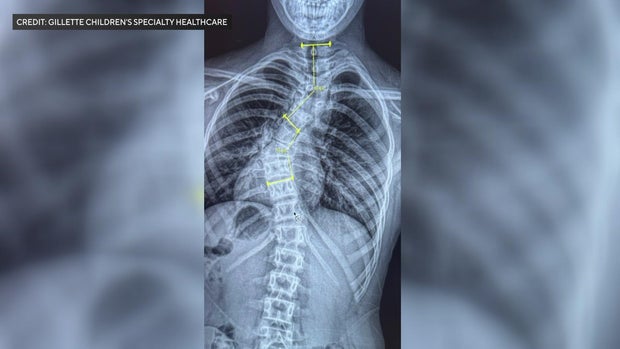

Her mom, Stefanie, brought her in to a doctor and when the X-rays came back, they were shocked to find a 56-degree curve in her spine.

"Even seeing her X-ray, it looked like it was broken. It didn't even look like scoliosis. It didn't look like anything I had seen before," Stefanie said.